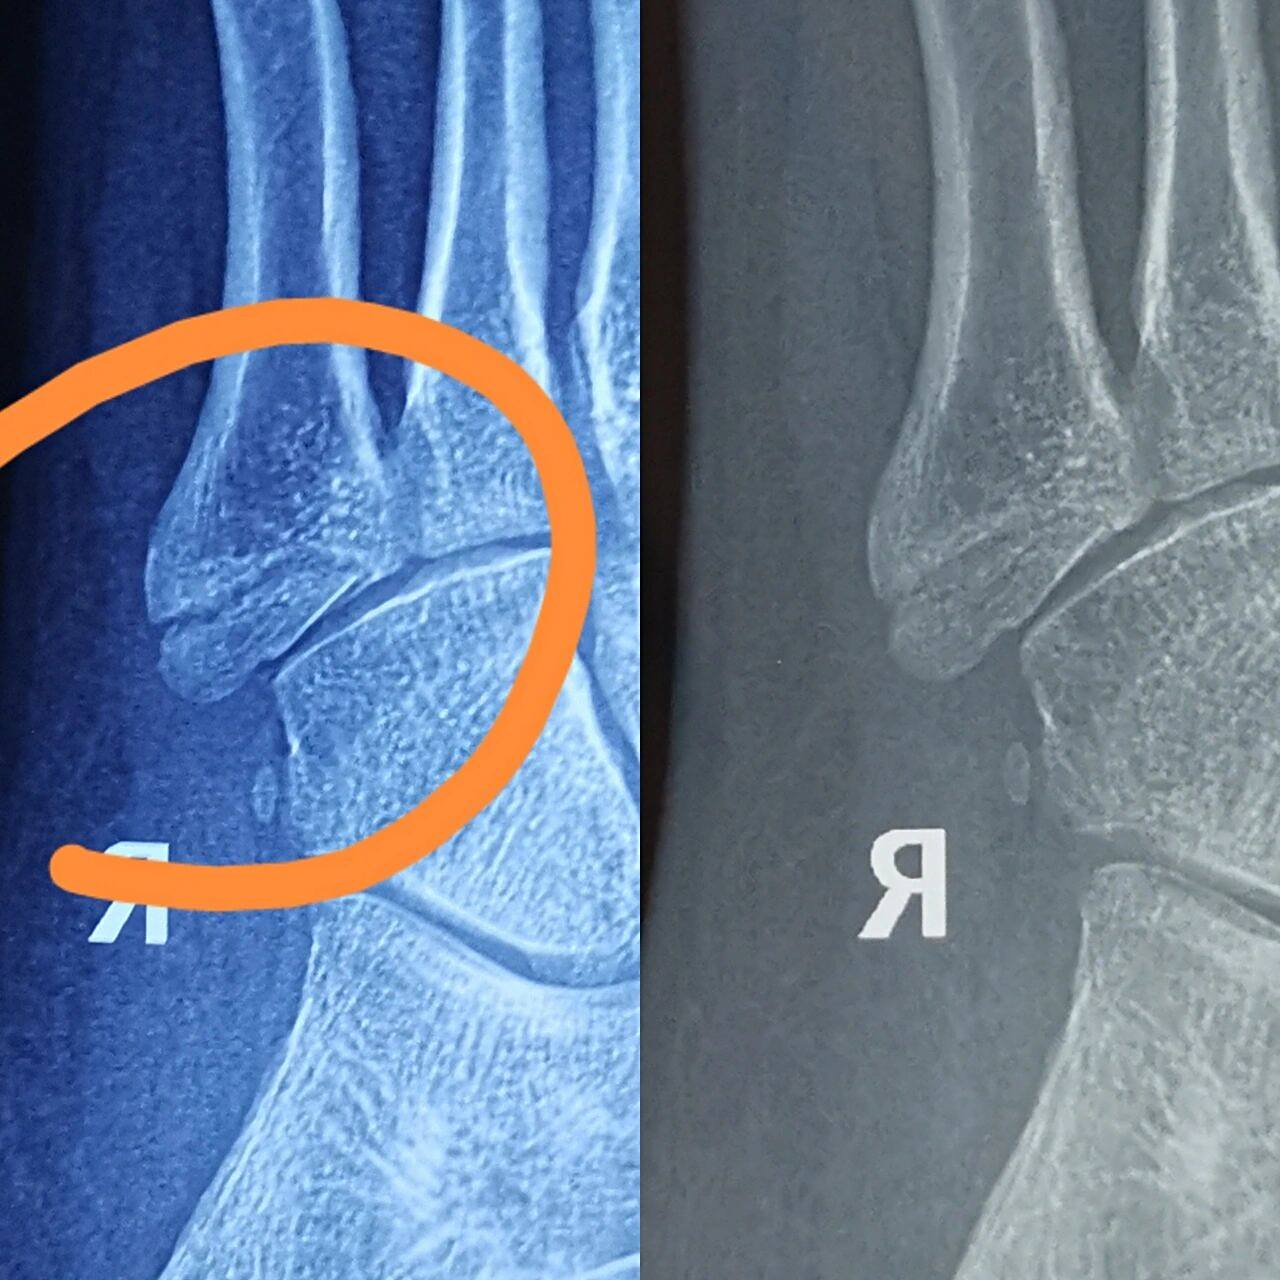

左足第四趾近节趾骨头骨折,长时间依然没有完全复位,该如何治疗,恢复